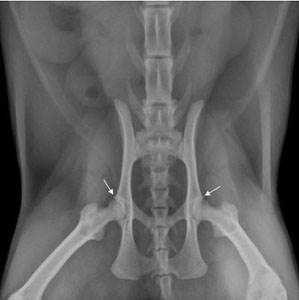

У некоторых кошек с ДТБС, особенно у кошек с тяжелым течением болезни, проявляются явные симптомы и болезненность. Эти кошки выглядят напряженными во время движения, неохотно прыгают и лазают. Время от времени они хромают. В некоторых случаях симптомы начинают проявляться после травмы, например, после падения. При проявлении у животного клинических признаков, похожих на ДТБС, необходимо уточнить диагноз с помощью рентгеновского исследования тазобедренных суставов. Ветеринарный врач может распознать разные вариации аномалий в тазобедренных суставах, связанные с дисплазией. В некоторых случаях сустав бывает частично или полностью подвывихнут.

Заводчики собак во избежание дисплазии тазобедренных суставов выполняют длительную скрининговую проверку животных и только потом включают их в программу разведения. У кошек в возрасте до двух лет можно только предварительно оценить заболевание, окончательный диагноз ставится уже по достижении кошкой этого возраста. Исследование проводится с помощью рентгена и требует седации для того, чтобы достичь расслабления мышц и обеспечить правильную укладку.